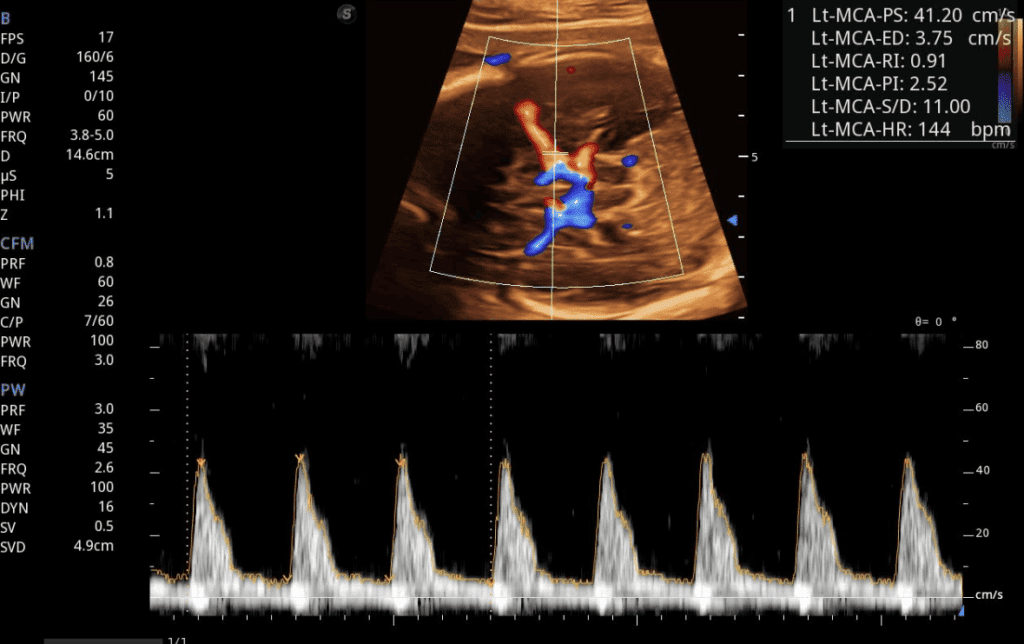

Perfil Hemodinámico

Estudio completo del flujo sanguíneo fetal que incluye arteria umbilical, cerebral media y ductus venoso para una evaluación integral del bienestar fetal.

Doppler Fetal

Evalúa el flujo sanguíneo del bebé durante el embarazo, monitoreando la circulación umbilical y cerebral para detectar posibles complicaciones y asegurar el bienestar fetal.